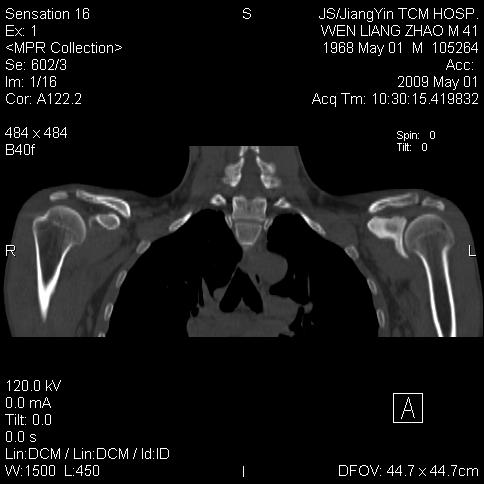

标题: CT19762:左侧喙突处压痛二年。考虑骨样骨瘤。 [打印本页]

标题: CT19762:左侧喙突处压痛二年。考虑骨样骨瘤。

左侧喙突处压痛二年。考虑骨样骨瘤。

病灶外缘膨胀明显,灶缘硬化较少,结合病史较符合骨母细胞瘤,其他亦不排除如软骨及软骨母细胞瘤等(病灶形态,成份较符合,发病部位也符合,只是年龄较大),骨样骨瘤多有较明显的自发性痛,且夜间痛明显,病史为压痛两年,不太符合.